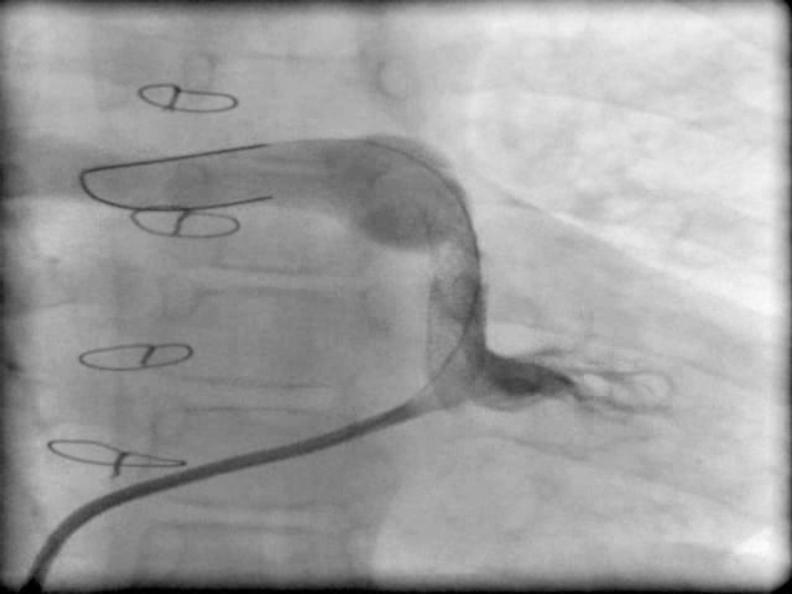

Native right ventricular outflow tract stenting in a child with tetralogy of fallot and absent left pulmonary artery.

Iran J Pediatr. 2014 Feb;24(1):119-21. Epub 2013 Nov 30.

PMID:25793059

原文链接:https://pmc.ncbi.nlm.nih.gov/articles/PMC4359597/

Native right ventricular outflow tract stenting in a child with tetralogy of fallot and absent left pulmonary artery.法洛四联症合并左肺动脉缺如患儿的右心室流出道原位支架植入术

A different therapeutic strategy for severe tetralogy of Fallot with origin of the left pulmonary artery from the ascending aorta: stenting of the right ventricular outflow tract before complete repair.一种针对左肺动脉起源于升主动脉的重症法洛四联症的不同治疗策略:在完全修复前对右心室流出道进行支架置入术。